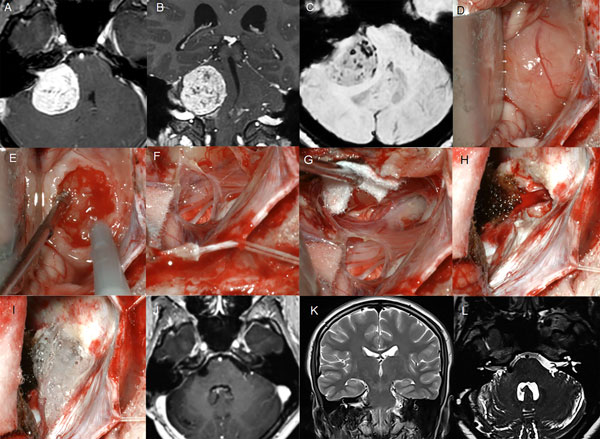

Figura 5: Paciente masculino de 18 años, operado de SV T4b bilateral. A-C: RM cerebral preoperatoria. D-I: imágenes intraoperatorias (lado derecho), D-F descompresión intratumoral con aspirador ultrasónico, G-H descompresión del complejo VII-VIII, I: oclusión del CAI con cola de fibrina., J-L: RM cerebral postoperatoria

Figura 6: Paciente femenino de 72 años, operado de SV T3b con quiste externo. A-C RM preoperatoria, D-I: imágenes intraoperatorias, D-F descompresión intratumoral con aspirador ultrasónico, G-H descompresión del complejo VII-VIII, J-L: RM cerebral postoperatoria.